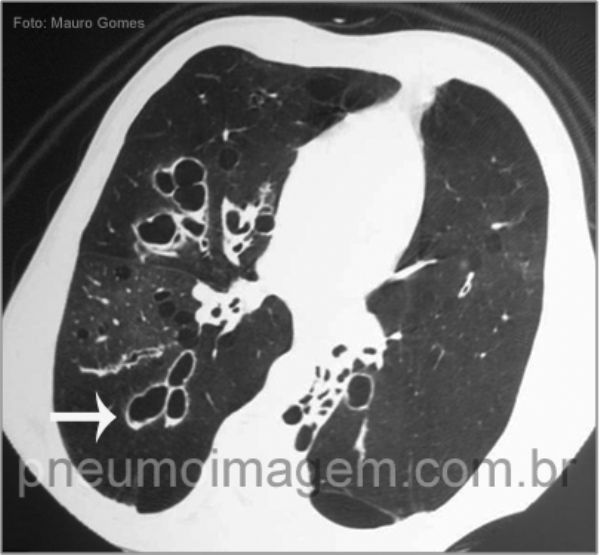

Neste corte tomográfico referente ao mesmo paciente da imagem anterior, observam-se extensas bronquiectasias centrais (seta branca) associadas ao padrão de perfusão em mosaico, que pode ser atribuído ao aprisionamento aéreo provocado pela doença.

Central bronchiectasis (white arrow) associated with the pattern of mosaic perfusion, which may be due to air trapping caused by the disease.